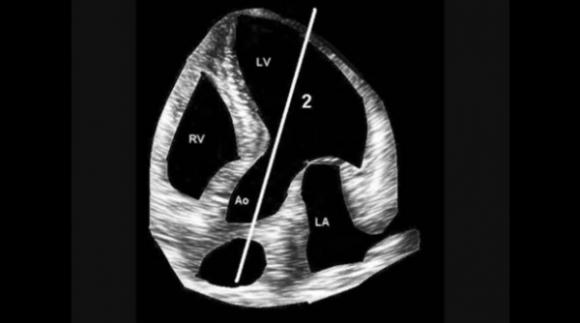

El estetoscopio Doppler funciona mediante la apreciación de la velocidad con que se mueven las estructuras y la sangre: se manda una onda de determinada frecuencia y se mide la diferencia con la que vuelve. Como esas variaciones se hallan en el orden de los Hertz, son directamente audibles con el oído humano. Lo que es necesario es saber, es en dónde hay que explorar el corazón y qué significan los sonidos.